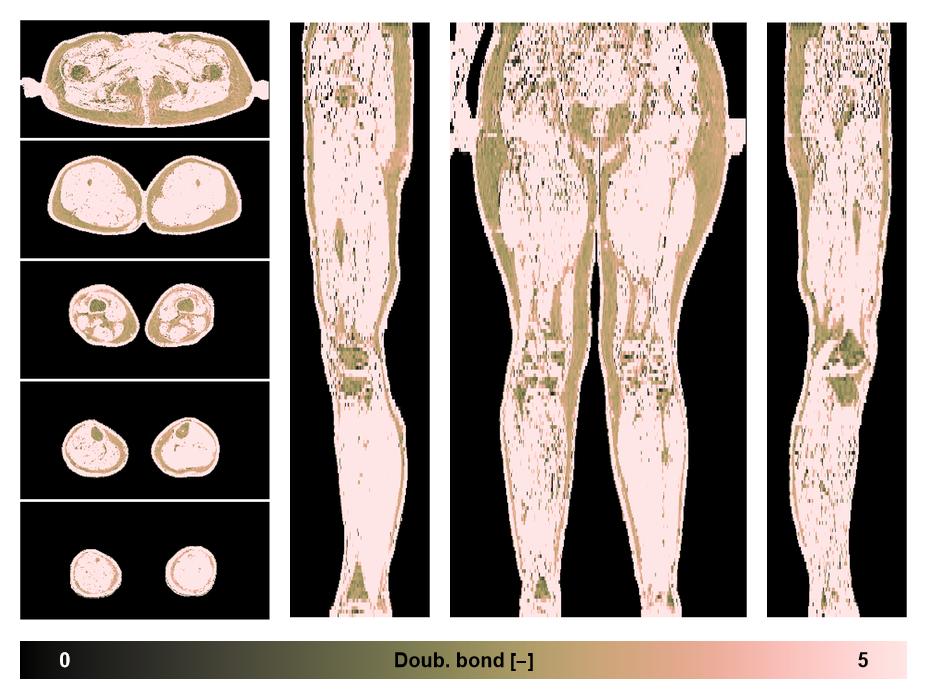

• Number of double bonds in subcutanious fat

Number of double bonds in subcutanious fat.